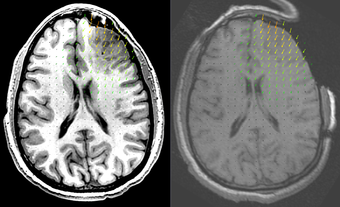

2. Create a B-Spline transform based on two sets of points read from files. These files can contain the initial and deform configurations for a biomechanics-based FEM or mesh-free registration. The resulting B-Spline transform can be used to warp 3D images, a process which is very time consuming if spatial interpolation is performed using the mesh [1]. This module reduces the image warping time from hours to seconds.